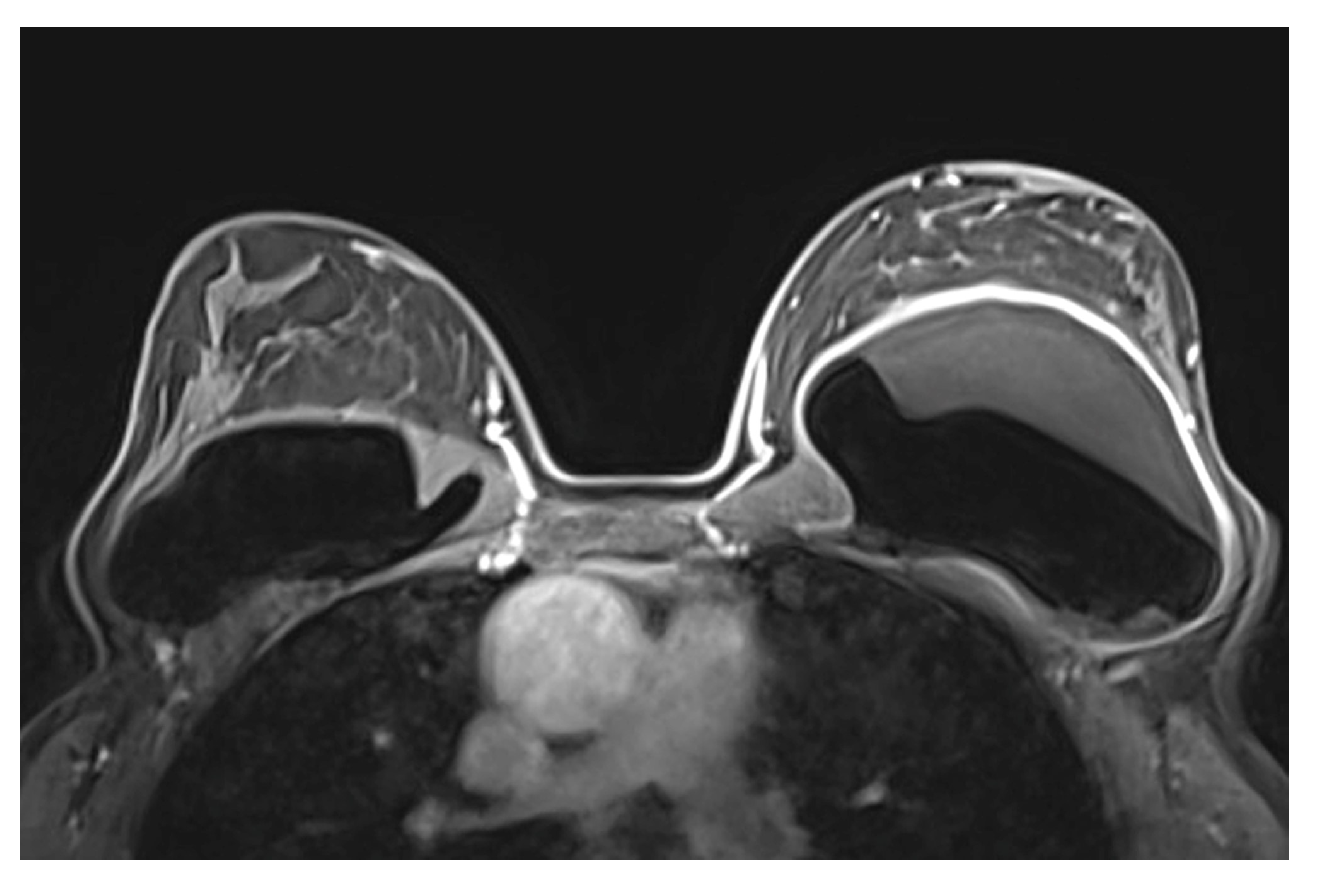

- Safvi, A. Linguine sign. Radiology 2000, 216, 838–839. [Google Scholar] [CrossRef]

- Soo, M.S.; Kornguth, P.J.; Walsh, R.; Elenberger, C.; Georgiade, G.S.; DeLong, D.; Spritzer, C.E. Intracapsular implant rupture: MR findings of incomplete shell collapse. J. Magn. Reson. Imaging 1997, 7, 724–730. [Google Scholar] [CrossRef] [PubMed]

| Definitive rupture | Linguini sign | Low signal lines within the silicone |

| Subcapsular lines | Low signal lines parallel to the capsule surrounded by silicone | |